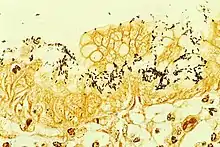

H. pylori colonized on the surface of regenerative epithelium (Warthin-Starry silver stain)

Colonization with H. pylori is not a disease in itself, but a condition associated with a number of stomach diseases.[28] Testing is recommended if peptic ulcer disease or low-grade gastric MALT lymphoma (MALToma) is present; after endoscopic resection of early gastric cancer; for first-degree relatives with gastric cancer, and in certain cases of dyspepsia.[108] Other indications that prompt testing for H. pylori testing include long term aspirin or other non-steroidal anti-inflammatory use, unexplained iron deficiency anemia, or in cases of immune thrombocytopenic purpura.[109] Several methods of testing exist, both invasive and noninvasive.